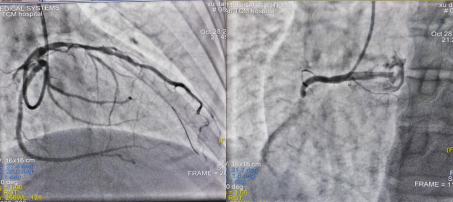

图1 术前前降支造影图2 术前右冠造影

图3 治疗后前降支造影图4 治疗后右冠造影